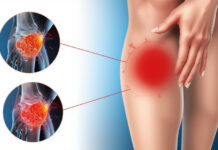

Swelling, Bruising, or Discoloration:

Although swelling is a normal reaction to an injury, it may indicate a fracture if it lasts longer than 24 to 48 hours. Swelling is a common side effect of fractures, albeit it might take hours for some types of fractures to develop and can be exceptionally mild.

Muscular spasms may cause additional pain as the muscles around the wounded area attempt to hold a shattered bone in place.

When bleeding occurs beneath the skin, bruises develop. The source of the bleeding could be nearby tissues or blood vessels within the broken bone. The bruise is initially purplish-black in colour, but when the blood is broken down and reabsorbed into the body, it gradually turns green and yellow in colour. A large bruise, or one that appears far from the injury site, can occur when blood travels away from the fracture.

But the reabsorption of the blood may take several weeks. The surrounding structures may experience transient pain and stiffness as a result of the blood. For example, a fracture in the shoulder can lead to discomfort in the wrist and the elbow, along with bruising on the arm.

It’s a warning sign that something more serious might be happening beneath the surface if the swelling continues to grow or becomes more uncomfortable to touch. You can determine if you have a fracture by consulting a medical professional.